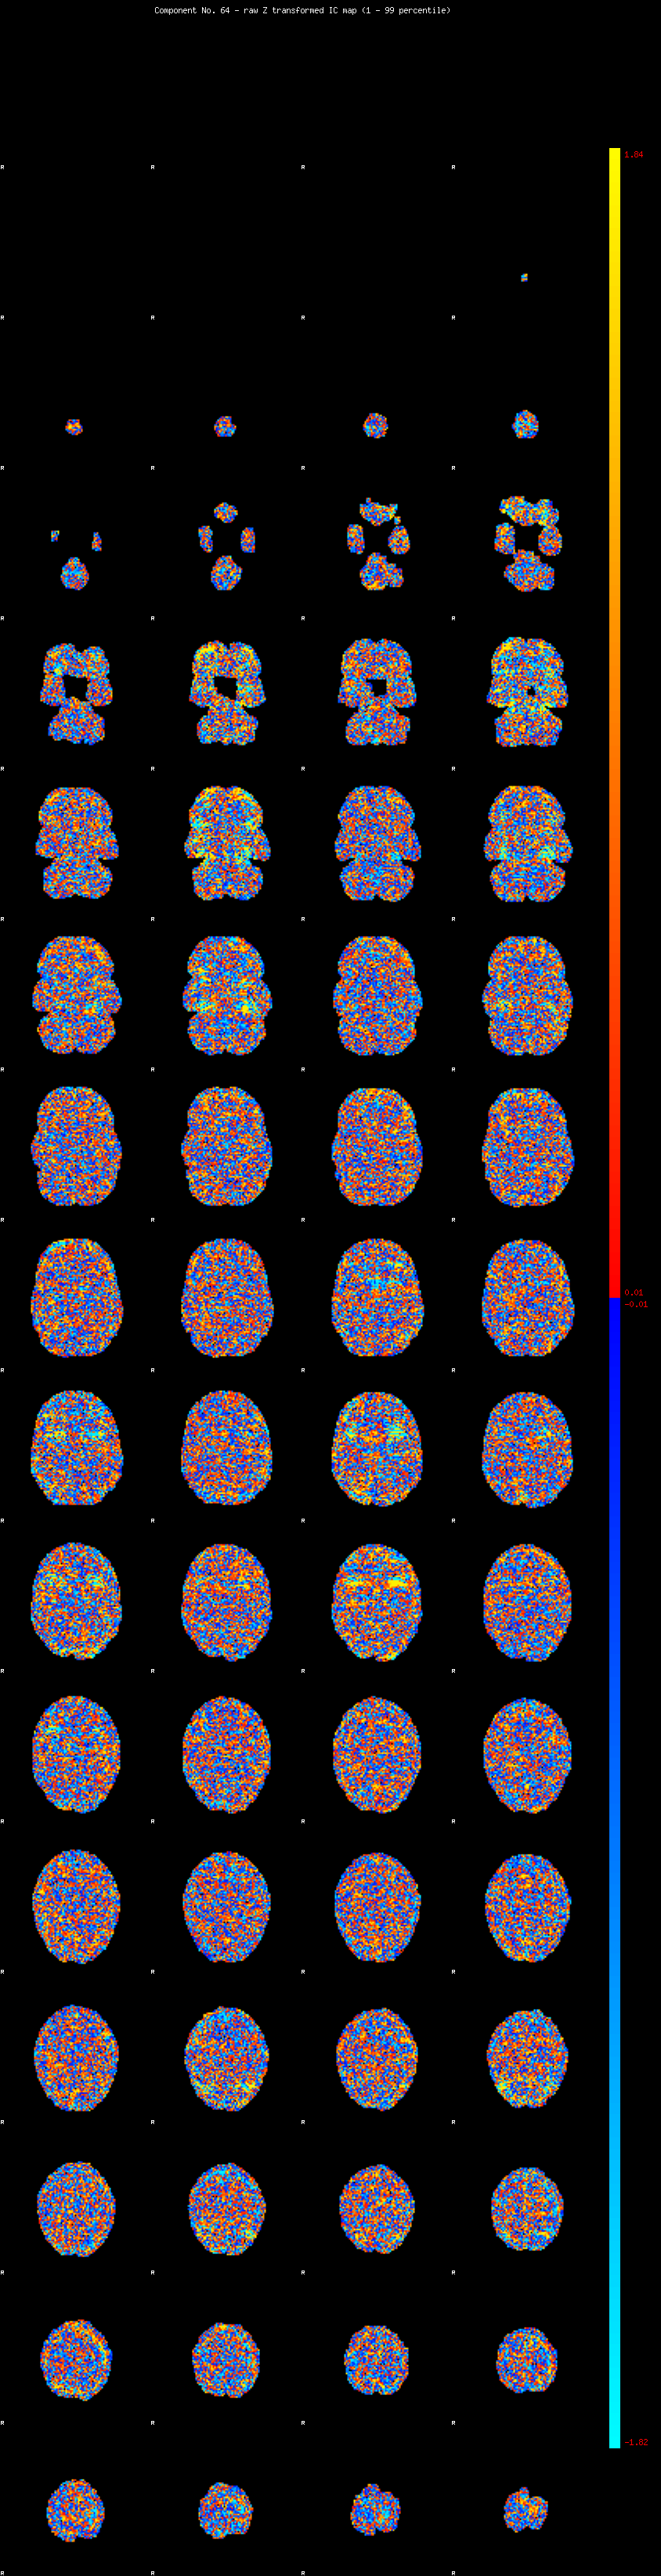

IC_64 Mixture Model fit

Means : -0.000000 2.393580 -2.228003

Vars : 1.000000 1.828110 1.341076

Prop. : 0.972583 0.014472 0.012946